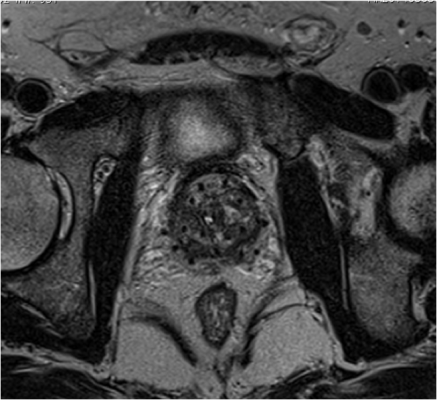

The study examined the patient-reported outcomes of 91 men with prostate cancer who received magnetic resonance imaging (MRI)-guided, vessel-sparing radiation at University of Michigan Providence Cancer Institute. The vessel-sparing radiation technique limits the amount of radiation to critical erectile tissues using MRI scans to identify the blood vessels responsible for erections. When radiation dose is limited to these critical structures, the risk of erectile dysfunction is lowered.

Of the 91 patients studied, all patients received EBRT. Forty-two of the patients received only EBRT (>77.8Gy), and 49 patients received EBRT plus brachytherapy, the implantation of radioactive seeds near the prostate. The combination patients received brachytherapy in the form of an I-125 permanent prostate implant. None of the patients received androgen deprivation therapy (ADT).